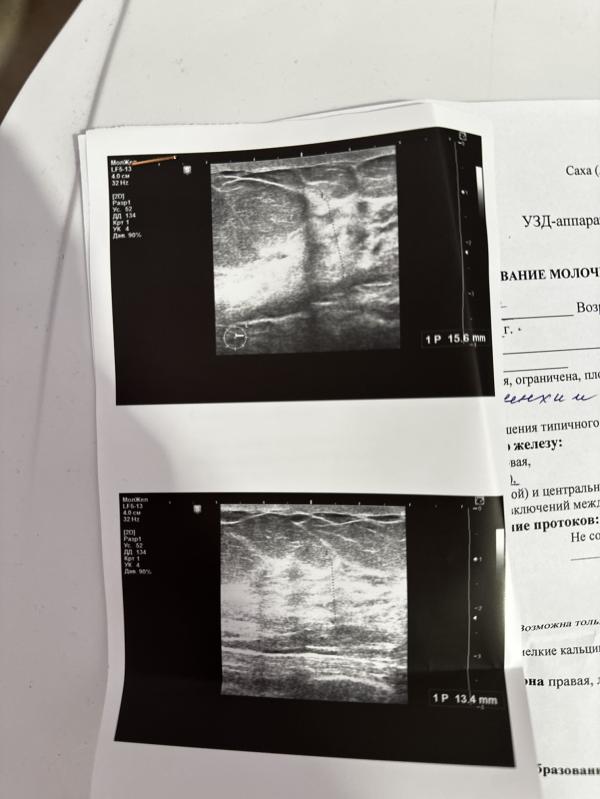

Фиброаденома бьлх ди? Быччахай курдук дуо? Я лет 10 назад удаляла в платной клинике. Медцентрга маммологка игин сырыппытым. Только вот не помню кто направлял🤔 гинеколог ду терапевт ду этэ

Идите к маммологу, я при фиброзной кистозной мастопатии просто наблюдаюсь и пью маммолайн от болей в груди, с ним особо ничего и не беспокоит